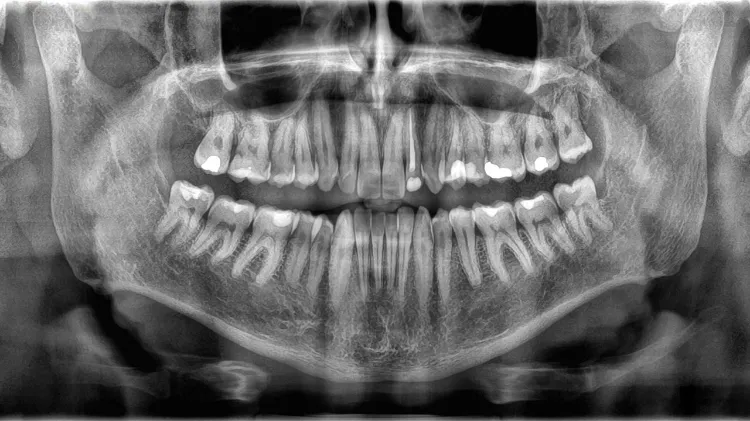

初看之下,牙齿与骨骼仿佛是天生的盟友。加州大学洛杉矶分校牙科学院的名誉教授埃德蒙·休利特博士一语道破了它们最初的交集:“它们都是矿化的组织。”确实,两者共享着由钙、磷等矿物质构成的坚硬基石——羟基磷灰石。这种晶体结构赋予了它们远超身体其他组织的硬度。然而,休利特博士紧接着说:“坦率地讲,它们的相似之处也就到此为止了。”这句转折,为我们揭开了一个隐藏在相似外表下的巨大鸿沟。牙齿隶属于消化系统,而骨骼则是支撑生命的骨架,它们从诞生之初,就被赋予了截然不同的使命。

使命的不同,决定了构造的迥异。牙齿的构造宛如一座精心设计的堡垒。最外层是牙釉质,这种由高达96%矿物质构成的组织,是人体最坚硬的物质,其硬度甚至超过骨骼。它是一件无生命的“盔甲”,一旦磨损或破损,便无法自行修复。盔甲之下是牙本质,它构成了牙齿的主体,硬度稍逊,但其内部遍布着连接神经的微小管道,当牙釉质受损时,冷热酸甜的刺激便会通过这些管道直达内部,引发敏感和疼痛。堡垒的核心,则是牙髓——牙齿唯一“活着”的部分。这里充满了血管和神经,为牙齿提供营养,感知外界的信号。

而骨骼的构造,则更像一座持续运转、不断改建的动态工厂。它的表面覆盖着一层薄而坚韧的骨膜,上面布满了血管和神经,为骨骼的生长和修复提供养分。骨膜之下是致密的皮质骨,提供了强大的支撑力。而骨骼的内部,则是海绵状的松质骨,其网状结构不仅能有效分散压力,更容纳着前面提到的“造血工厂”——骨髓。从外到内,骨骼的每一个角落都充满了生命的脉动。

构造的差异,最终指向了两者最本质的区别——生命力。牙齿的生命,更像是一幅在胚胎时期和童年就已完成并定格的画作。负责制造牙釉质的“工匠细胞”——成釉细胞,在完成这件坚硬的艺术品后便会凋亡。这意味着,牙齿一旦成型,它的外部结构就失去了再生的能力。尽管牙髓是活的,但它无力回天,无法帮助修复外层的牙釉质或牙本质。因此,每一次损伤都是一次永久的记录。

骨骼的生命,则是一首永不停歇、终身重塑的交响乐。它是一个充满活力的动态系统,体内时刻上演着“破旧立新”的循环。破骨细胞负责分解陈旧的骨组织,而成骨细胞则负责建造新的骨组织。这个过程被称为“骨重塑”。得益于此,我们的骨骼能够在一生中不断适应身体的压力变化,骨折后能够自我修复,甚至整个成年人的骨架大约每十年就会彻底更新一次。骨骼是活的,它在不断地与我们的生命互动、共同成长。